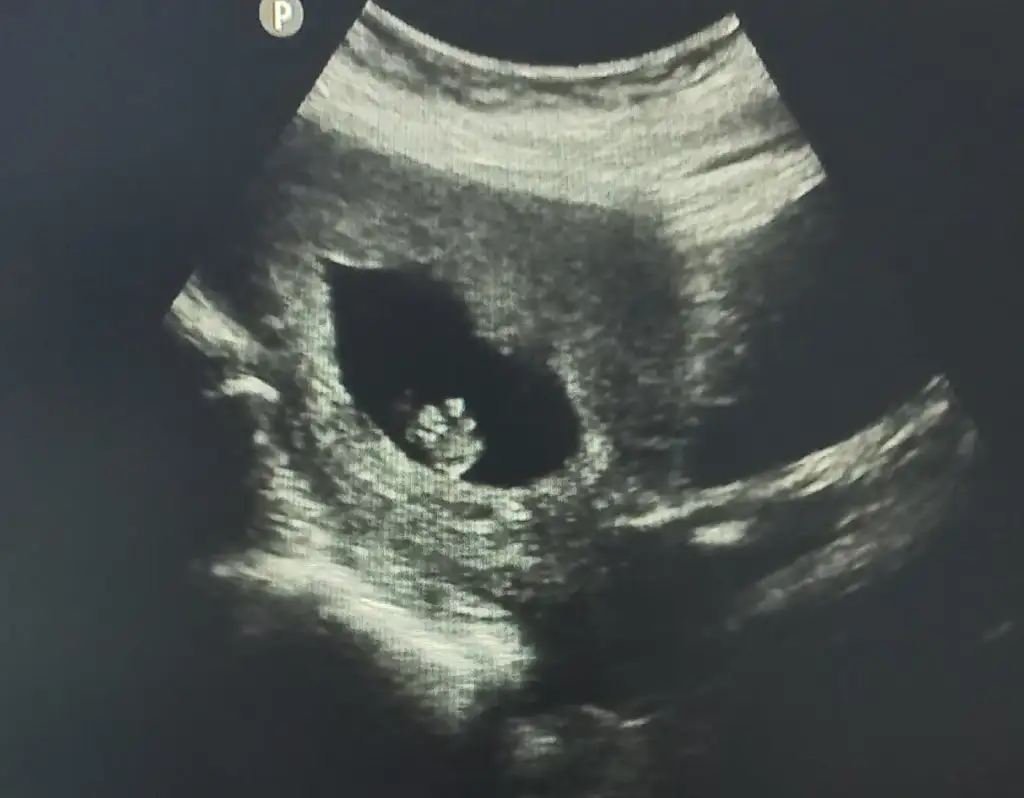

senin beta 600lerde gittin dimi ? Ben bugün kan verdim 1162 çıkmış 2 gün sonra randevum var Allah izin verir de en az 2 kat artmis olursa 2300 fln oluyor inşallah görebilirim nokta bile olsa

oo sen o değerle kalp atışını bile duyarsın inşallah içini ferah tut